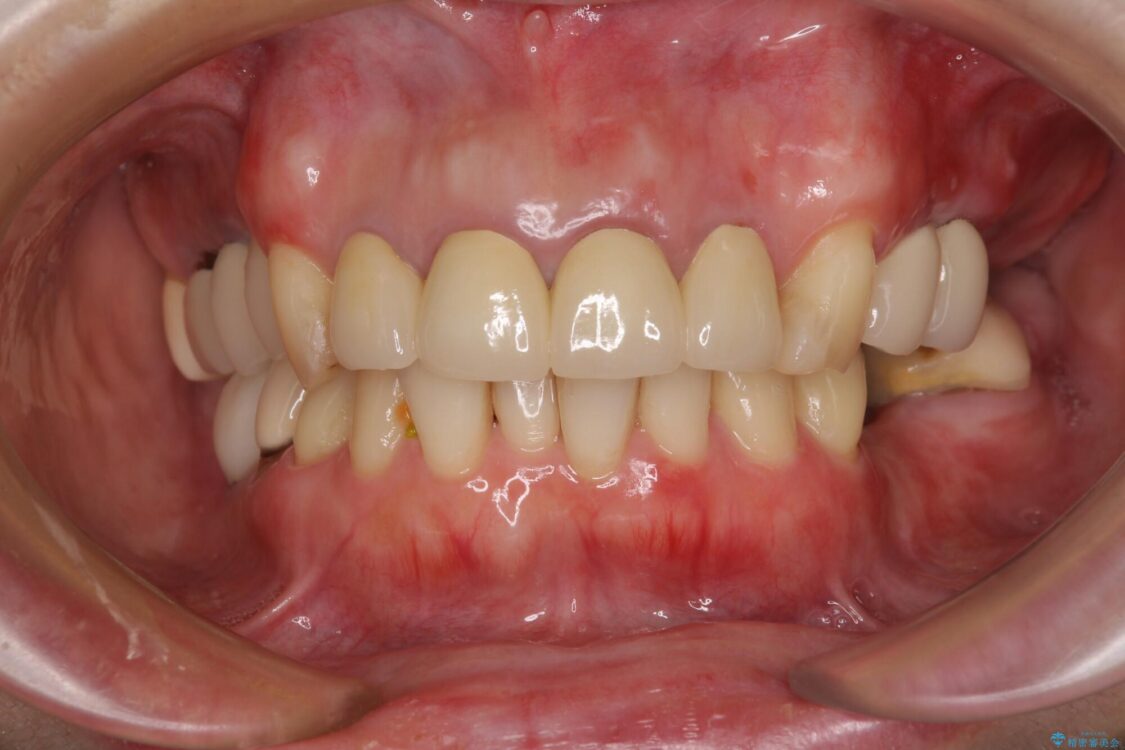

治療後について

日頃の歯磨きをしっかりと行ってくださるので、新しい仮歯に変えてから速やかに歯肉の状態が改善されました。

歯肉からの出血がほとんどないため精度の良い型取りができ、非常に適合の良い補綴治療を行うことができました。

治療後

• 仮歯のまま放置した前歯 オールセラミッククラウンで自然な前歯に 治療後画像